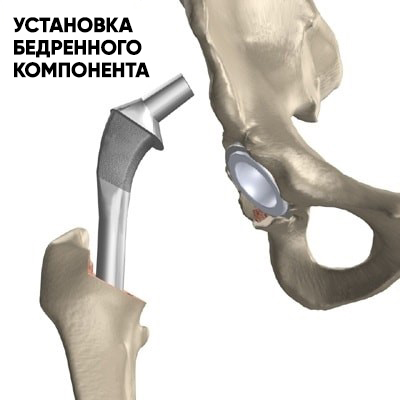

После застывания цемента и фиксации вертлужного компонента, хирург приступает к бедренной кости. На данном этапе производится разработка костного канала бедренного канала специальными рашпилями до требуемого размера. Далее в подготовленный канал в бедренной кости помещается цемент и устанавливается бедренный компонент.